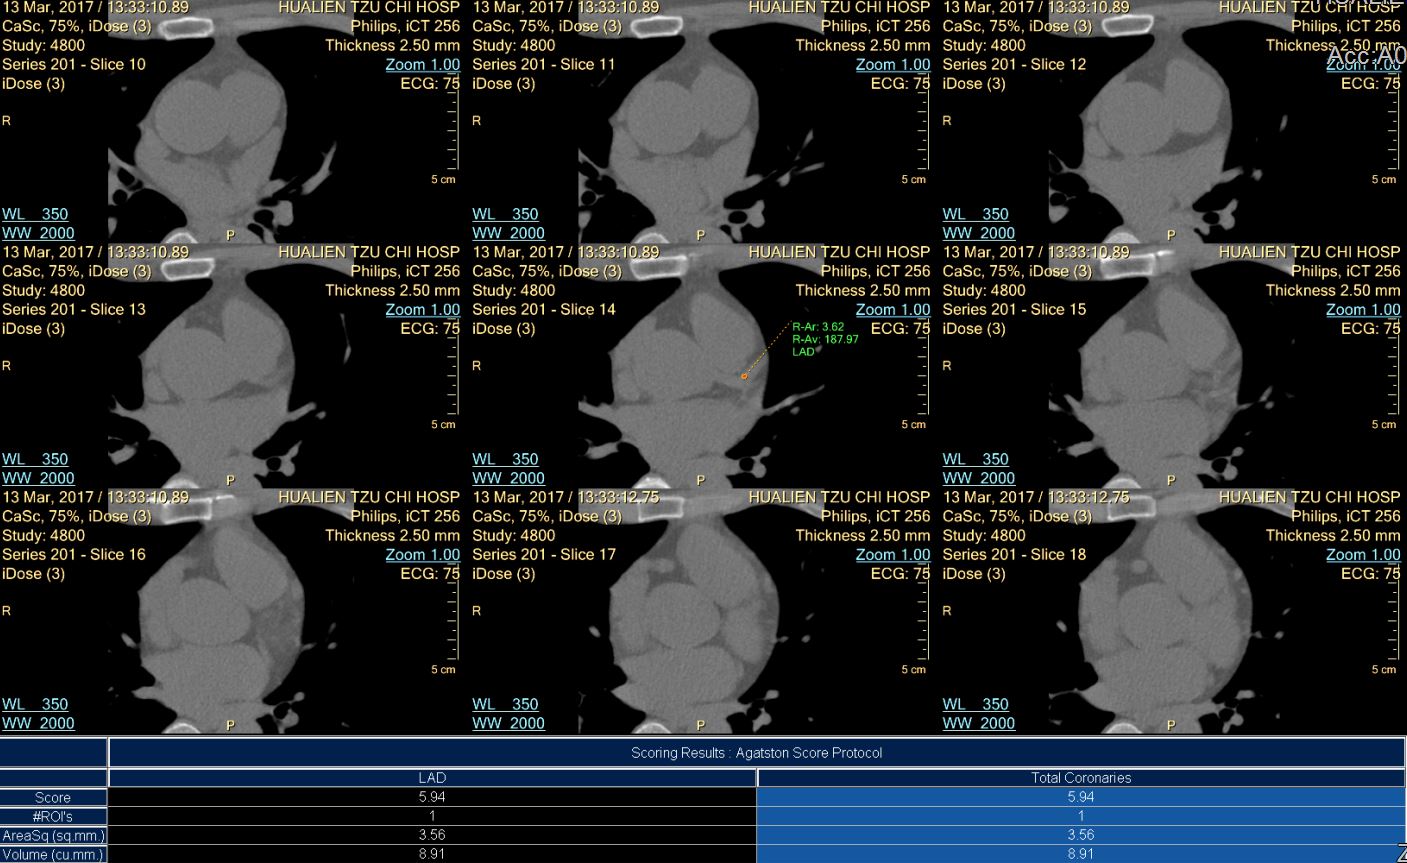

3. 冠狀動脈鈣化分析(CACS: Coronary Artery Calcium Score)

冠狀動脈鈣化是血管上斑塊(脂肪沉積)或動脈粥樣硬化的標記。軟性斑塊發生較早也較不穩定,鈣化的斑塊則發生在後。這些鈣化堆積出現的時候要比發生心臟病症如胸痛及呼吸短促要早好幾年。

鈣化指數計量是用電腦依據每一條冠狀動脈鈣化沉積的容積和密度來計算,提供鈣化粥樣硬化斑塊的承載量以為參考。這個指數並非直接與血管的狹窄百分比一致,但是它與冠狀動脈粥樣硬化的嚴重度有密切關係。